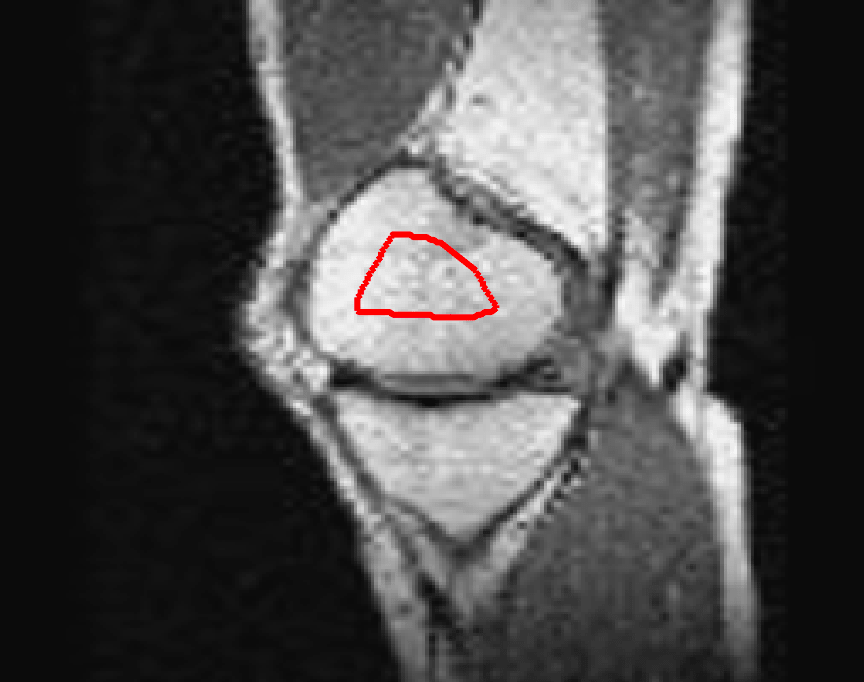

Test Images. We will perform initial tests on the images shown in Figs. 5–7. We have provided the ground truth and initialisation used for each image. Test Images 1–3 are synthetic, Test Image 4 is an MRI scan of a knee, Test Images 5–6 are abdominal CT scans, and Test Images 7–9 are lung CT scans. They have been selected to present challenges relevant to the discussion in §2. We focus on medical images as this is the application of most interest to our work. In the following we will discuss the results in terms of synthetic images (1–3) and real images (4–9). We also test the proposed approach on a larger data set of 30 CT images (a sample of which is presented in Fig. 18), comparing against existing selective methods detailed in §3.

Real Images. In Fig 12 we present results for Test Images 4–6. Here, the proposed model performs in a similar way to its competitors because these images are more typical selective segmentation problems in the sense that there is a clear distinction between the foreground and background intensities. In particular, the values in each case are: Test Image 4 , Test Image 5 , and Test Image 6 . It can be seen that the proposed model is competitive compared to previous approaches. The performance is quite poor for Test Image 5, but is arguably still the best for this challenging case. In Fig. 13 we present results for Test Images 7–9. Here the proposed model outperforms previous approaches significantly for each image. This is mainly due to the type of image considered. Specifically, the true intensities are: Test Image 7 , Test Image 8 , and Test Image 9 . The proposed model is capable of achieving results where , with other models failing completely in these cases.

Synthetic Images. We observe that for Test Images 1 and 2 (where , CV, LCV, and HYB fail completely. GAV performs well, with the proposed model and RSF being the most accurate with perfect results. For Test Image 3, all models are capable of achieving a good result. It should be noted that in this case and . This difference enables the other models to perform well, although the proposed model is slightly superior with a perfect result. The alternative selective models also perform well for these images, although CAC has minor errors on the boundaries of the foreground for each image.

Real Images. In Table 1 we can see that the proposed model is the most successful in terms of optimal accuracy. It is worth noting some inconsistency in the other models, with all but GAV having results that fall below TC for at least one image. GAV performs well for Test Images 4–9, with the proposed model slightly outperforming it in each case. It is worth reminding the reader that for GAV the parameters have been refined for each example. Fixing this results in more variability in the quality of results. The proposed model has no such parameter optimisation between examples. CAC and SRW perform reasonably well for these images, although are sometimes substandard for Test Images 4-7. This is despite extensive refinement of the user input to achieve an acceptable result. We present the optimal results for Test Image 9 in Fig. 14. Here we can see how much variation there is in the quality of results for this lung CT image. CAC and SRW are competitive in this instance. Of the remaining approaches GAV is the most competitive (TC ), but is visually inadequate. Two other models (CV, HYB) fail completely. In this case, the problem looks quite straightforward and yet other fitting terms are insufficient to produce a good result. Again, the proposed model tends to be superior in cases where and is capable of achieving very good results for all the images considered. This highlight the advantages of the proposed fitting term.